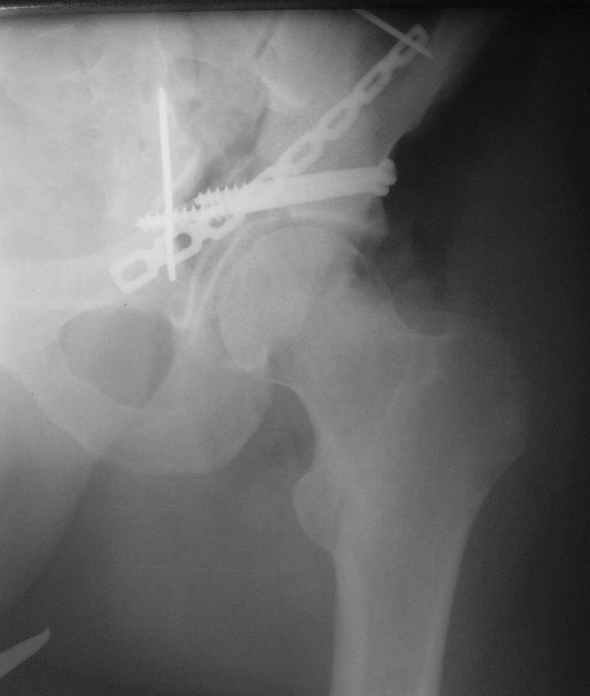

Не дождавшись советов, в понедельник прооперировал больного, заняло времени..., но все сделал в один этап: сначала фиксировал ипсилатеральный перелом бедра и шейки реконструктивным гвоздем Smith&Nephews, потом из расширенного илеофеморального доступа фиксировал перелом крыла подвздошной кости тягловым винтом, нейтрализующей пластиной заднюю колонну, и тягловыми винтами 3,5 мм переднюю колонну.

Несмотря на расширенный доступ, особой кровопотери не было, перелил только одну дозу эр.массы и на утро Нв- 10.5 и как ни странно больной не жалуется на сильные боли и стопа не *висит*, хотя при интраоперационной ревизии седалищного нерва обширная гематома в периневральной оболочке.

К сожалению, набора для ретроградного или антеградного реконструктивного штифтования в операционной нет, поэтому доставка заняла н-ное время. Вопрос, который возник у меня- по поводу оптимальной тактики хирургии: вся фиксация в один этап из расширенного доступа или последовательно сначала бедро и позже реконструкция впадины, комбинированный доступ к впадине отдельно к передней и задней колоннам или из расширенного илеофеморального одного доступа. Все-таки решил остановиться на одноэтапном подходе и спустя 5 дней (как раз и наборы привезли) из расширенного илеофеморального доступа сначала фиксировал реконструктивным штифтом Smith&Nephews бедро и

шейку (благо перелом шейки 2 типа -относительно стабильный) затем фрагмент крыла подвздошной кости Lag screw, далее пластина на заднюю колонну и винты в переднюю колонну.(с размерами и направлением винтов ошибка вышла:-((, но интраоперационно у меня была полная уверенность , что винты *ушли* в лонную кость).

Еще раз спасибо за комментарии и готовность помочь с имплантами. Постоп картинки в приложении,